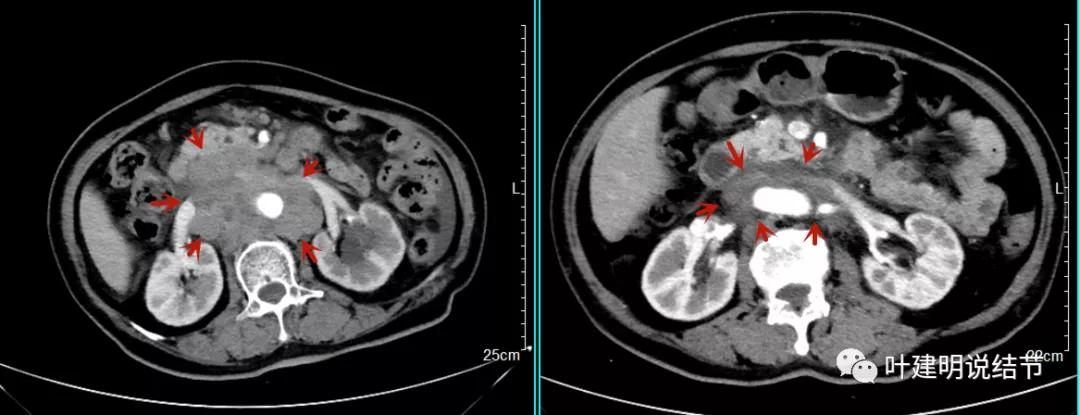

之后又再经过一个周期后的对比:

上图同样左侧是治疗前的,右侧经过2周期免疫加化疗后复查的,可见病灶缩小甚至超过9成。下面是治疗前与后来于6月底复查的: